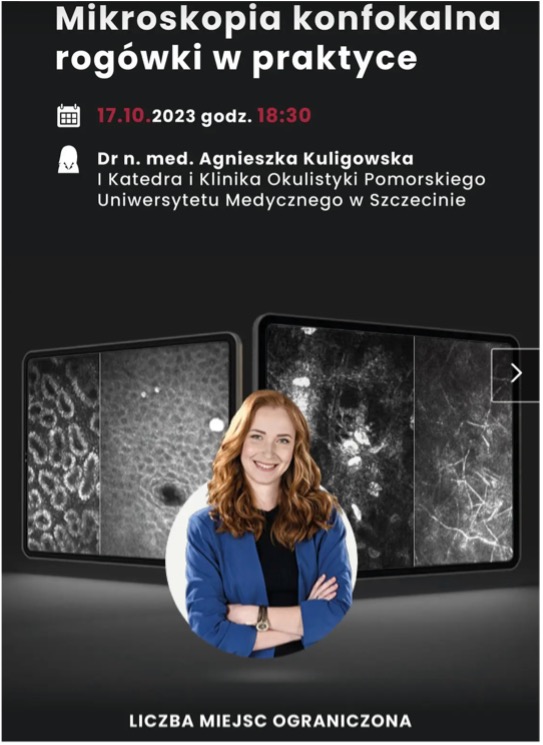

- Poprowadziliśmy pierwszą edycję kursu z zakresu chorób powierzchni oka i podstaw keratoplastyki dla lekarzy w trakcie specjalizacji z okulistyki, a także szkolenie z zakresu mikroskopii konfokalnej dla okulistów z całej Polski.